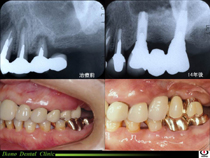

歯周病治療

歯周病  歯周病とは、「歯に付着した細菌」や「かみ合わせ」によって炎症が起こり、歯の周囲の歯ぐきや顎の骨といった、歯を支える組織が破壊されていく病気です。

歯周治療

歯周治療とメインテナンスで ずいぶん歯茎が引き締まり、しっかりしてきました。患者さんの自己管理と、PMTCや定期健診のような術後管理がうまくいってはじめて成功といえます。 継続的な管理が大切なのは高血圧や糖尿病と似ています。

進行した歯周病の場合、 歯周病の治療はもちろんですが、再生療法、レーザー治療、矯正治療、咬合治療、審美歯科治療と総力を結集させることが求められます。

当院での治療例(クリックで拡大)